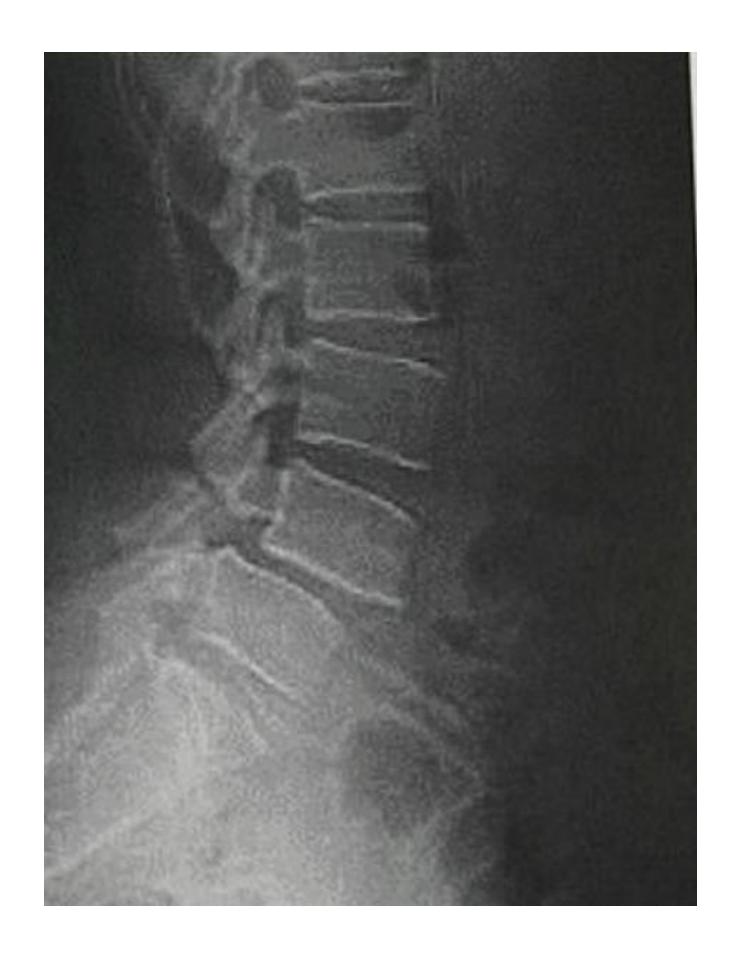

A 36-year old patient presented with low back pain for two years that has recently increased.

Q15: Write TWO abnormal findings you can see on the x-ray

- Slipped lumbar spine โ over the other lumbar spine โNot sure what is the vertebrae numberโ

Q16: What is the most probable complication?

- Nerve root injury